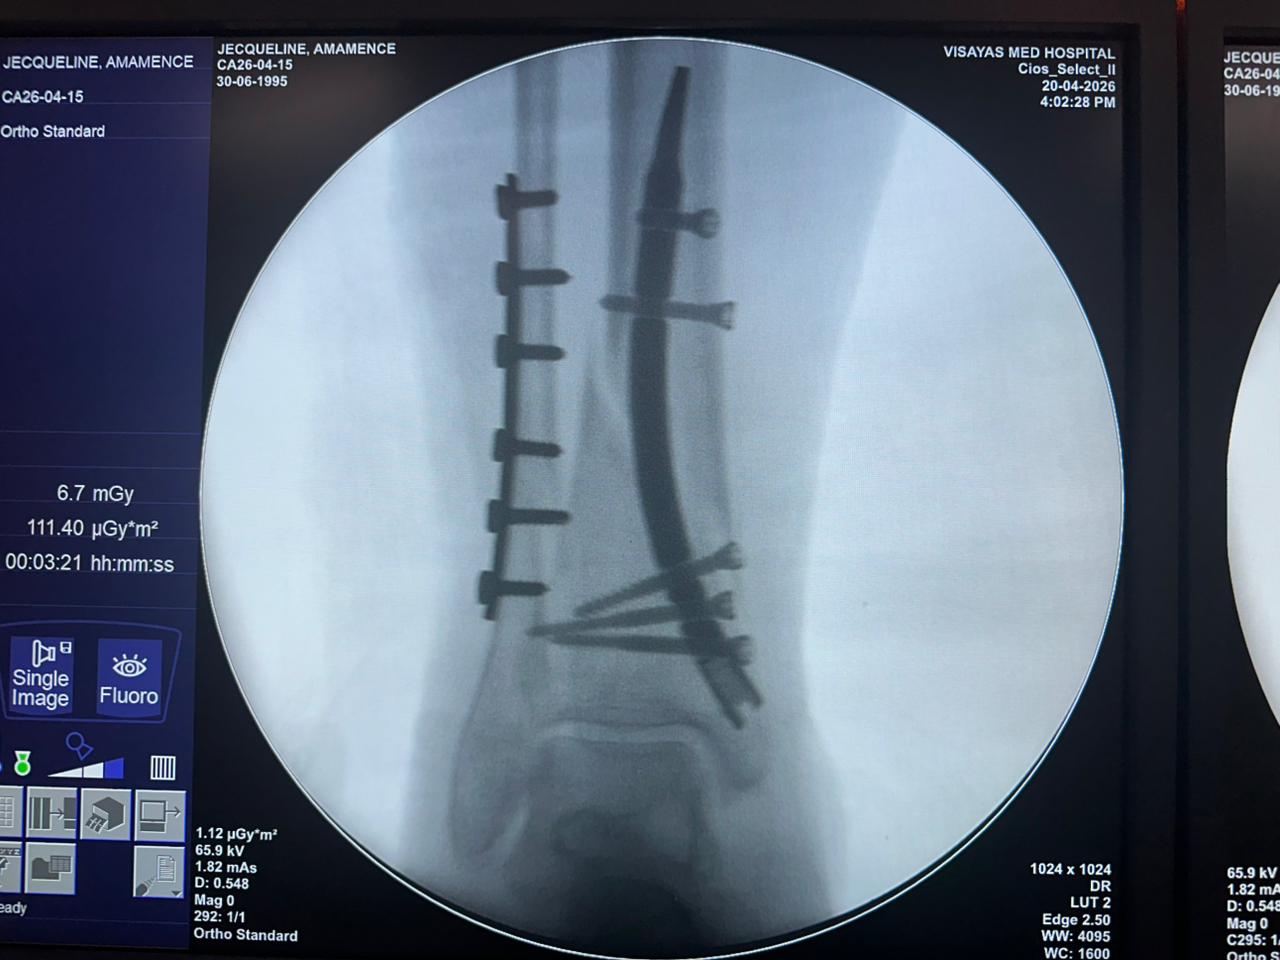

Caso di studio sulla fissazione del chiodo tibiale distale con supporto per placca peroneale

Paziente:

Paziente di 31 anni

Area Chirurgica:

Tibia e perone distali

Prodotto utilizzato:

Chiodo tibiale distale

Piastra di bloccaggio peroneale

Immagine:

Fluoroscopia intraoperatoria con arco a C, viste AP e laterali

Questo caso prevedeva la fissazione tibiale distale utilizzando un chiodo tibiale distale intramidollare. La fluoroscopia intraoperatoria ha confermato la posizione del chiodo, delle viti di bloccaggio distali e della fissazione della placca peroneale.